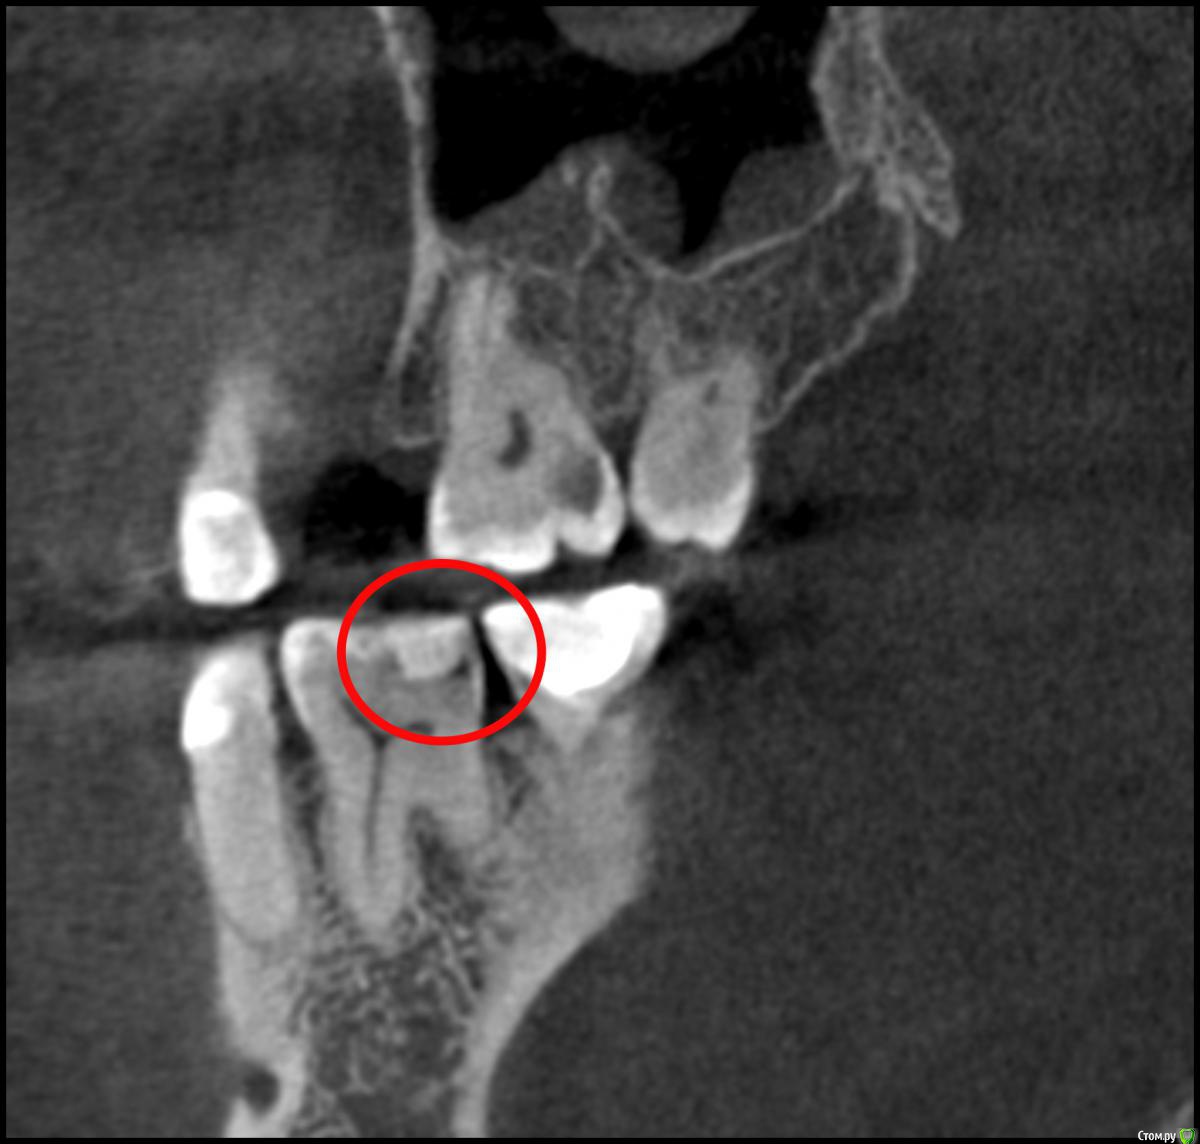

Nick-ev Опубликовано 6 апреля, 2019 Поделиться Опубликовано 6 апреля, 2019 2 месяца назад запломбировали зуб, не болел вообще, но стоматолог увидел что то на нем.Недавно делал КТ и увидел затенение под пломбой.Пожалуйста посмотрите, что это на снимке. Ссылка на комментарий

Nick-ev Опубликовано 8 апреля, 2019 Автор Поделиться Опубликовано 8 апреля, 2019 По кт кариес под пломбой диагностировать практически невозможно, его обычно делают в других целях а что это за темное пятно под пломбой? Ссылка на комментарий

___49___ Опубликовано 8 апреля, 2019 Поделиться Опубликовано 8 апреля, 2019 а что это за темное пятно под пломбой?Возможно кариес, возможно рентген не контрастный цемент или др материал .. Такого рода клинические случаи получают диагноз по совокупности данных объективных исследований, жалоб и клинических проявлений - что можно сделать только в кресле у врача. Коллега права - под пломбой диагноз по КТ весьма затруднителен, а вот зуб сверху над тем что вы указали с кариесом и диагноз тут очевиден , так как пломбы нет и рентген не контрастное вещество в него до нас не закладывали . Ссылка на комментарий